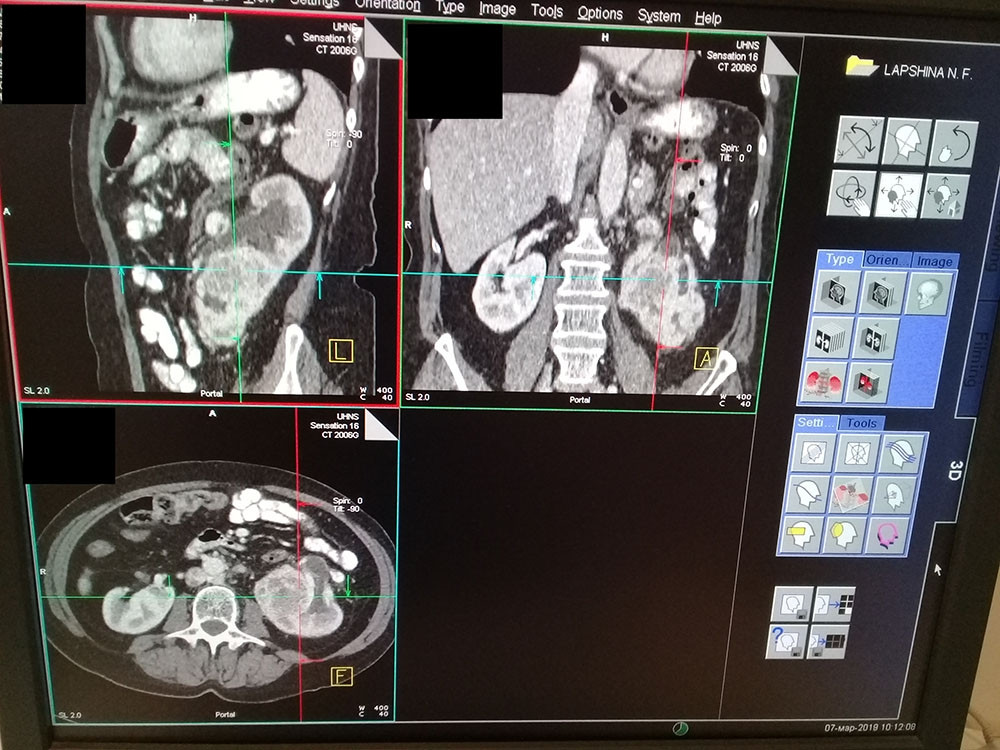

КТ-картина гиперваскулярного образования в нижнем сегменте левой почки с признаками прорастания на уровне соустья лоханки и мочеточника, с наличием опухолевого тромба в левой почечной вене. Окклюзионный гидронефроз слева.